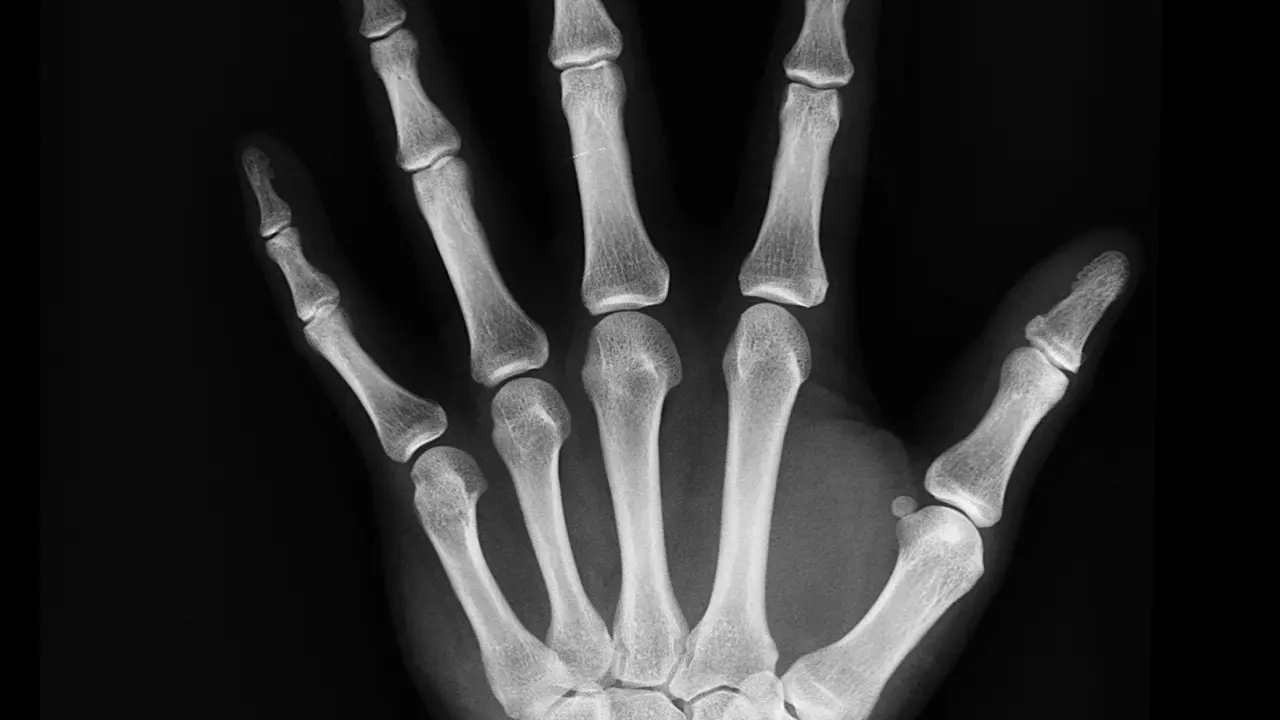

Bones Care Tips: इन चीजों को खाने से खोखली हो सकती हैं आपकी हड्डियां! फौरन बना लें दूरी

Health Care Tips: कुछ चीजों का सेवन करने से शरीर की हड्डियां धीरे-धीरे कमजोर पड़ने लगती हैं।

Weak Bones Care: हेल्थ दुरुस्त रखने के लिए शरीर की हड्डियों की सेहत का ध्यान रखना भी बेहद जरूरी होता है। हड्डियों की सेहत के लिए जरूरी है कि हम हमारे खान-पान का विशेष ध्यान रखें। हमारे खान-पान का सीधा संबंध हमारी सेहत से होता है। कई ऐसी चीजें हैं जिनका सेवन करने से हमारा शरीर और सेहत अच्छी बनी रहती है।

वहीं, कुछ ऐसी चीजें भी हैं जिनके सेवन से हमारे शरीर को कई तरह के नुकसान भी झेलने पड़ते हैं। शरीर पर पड़ने वाले इन नुकसानों में सबसे ज्यादा असर हमारी हड्डियों पर पड़ता है। जी हां, आपने महसूस किया होगा कि कई बार हमारे शरीर की हड्डियां बिना किसी कारण के कमजोर पड़ने लगती है। दरअसल, इसकी वजह हमारा गलत खान-पान होता है।